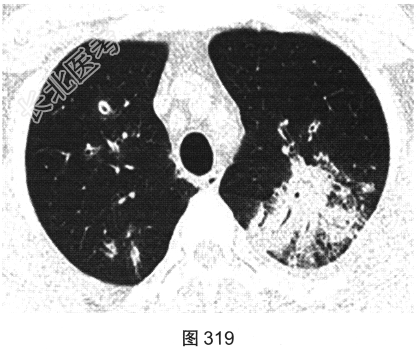

- [材料题] 患者男性,30岁,发作性咳喘3年,吸入冷空气后鼻塞、流黄白色脓涕,外院予环丙沙星治疗后症状缓解,其后鼻塞,夜间睡眠中喘憋反复发作;咯血、发热1周,以傍晚和夜间为著,体温最高为38.5℃,伴畏寒及周身疼痛,痰中带血,为鲜红色,伴胸痛、咳嗽,喘憋明显。胸部CT检查如图319~图324所示。

- 多项选择题1.在提供的CT平扫图像上,可观察到下列哪些影像学征象( )

A、晕征

B、双肺结节影

C、小叶间隔增厚

D、反晕征

E、小叶中心结节

F、双肺磨玻璃影、斑片实变影

G、支气管壁增厚、管腔扩张、支气管充气征